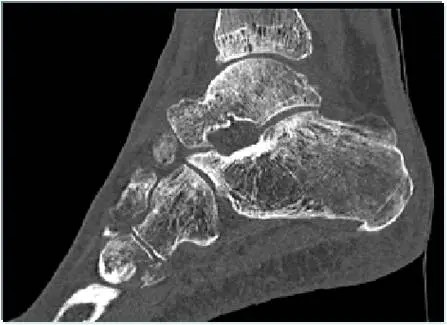

Spezialaufnahmen wie die Saltzman-Aufnahme oder Rückfußaufnahme können helfen die Rückfußachse zu beurteilen. In fortgeschrittenen Fällen und zur präoperativen Planung ist ggf. eine Schnittbildgebung in Form eines CT oder MRT sinnvoll,.

CT einer OSG Arthrose